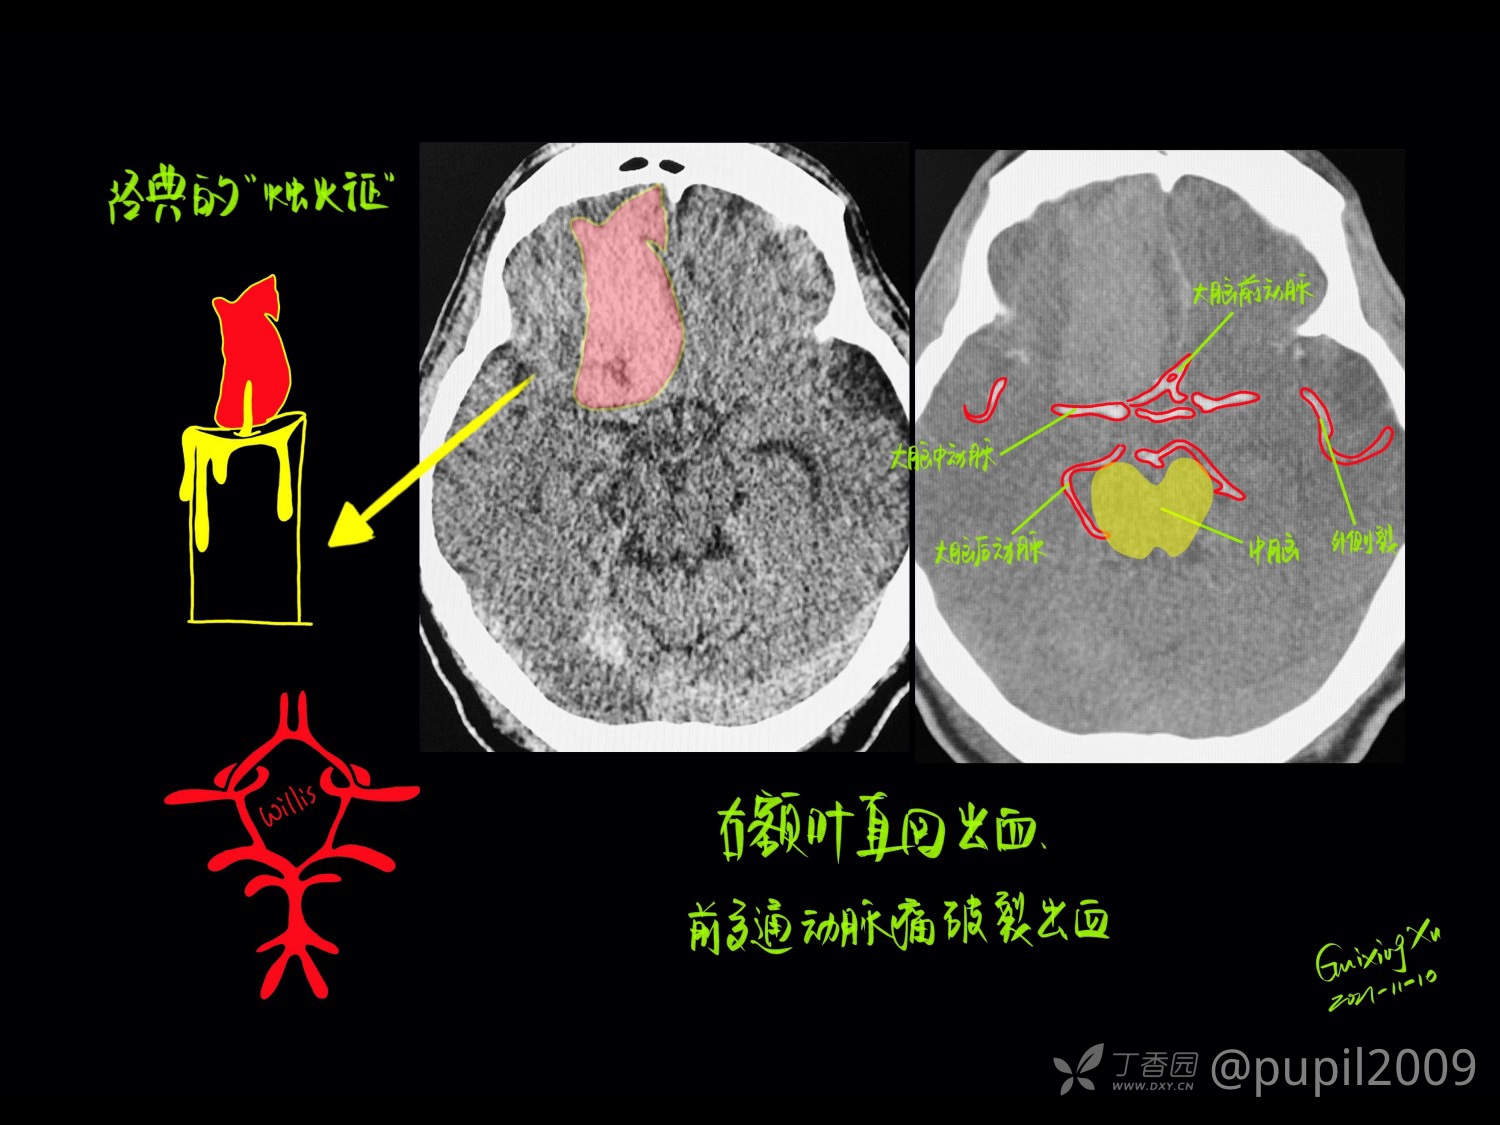

头颅连续断层解剖是通过逐层分析不同平面影像,研究颅骨、脑组织及血管等结构的空间关系,为医学影像诊断和神经外科手术提供精准定位依据。核心在于理解冠状、矢状、水平三个标准切面下的解剖层次,需结合CT、MRI等影像技术掌握关键结构的形态特征。对于医学学习和临床工作,理解头部CT断层解剖是解读影像、诊断疾病的基础。它是影像诊断从“看图”上升到“识病”的必备桥梁。